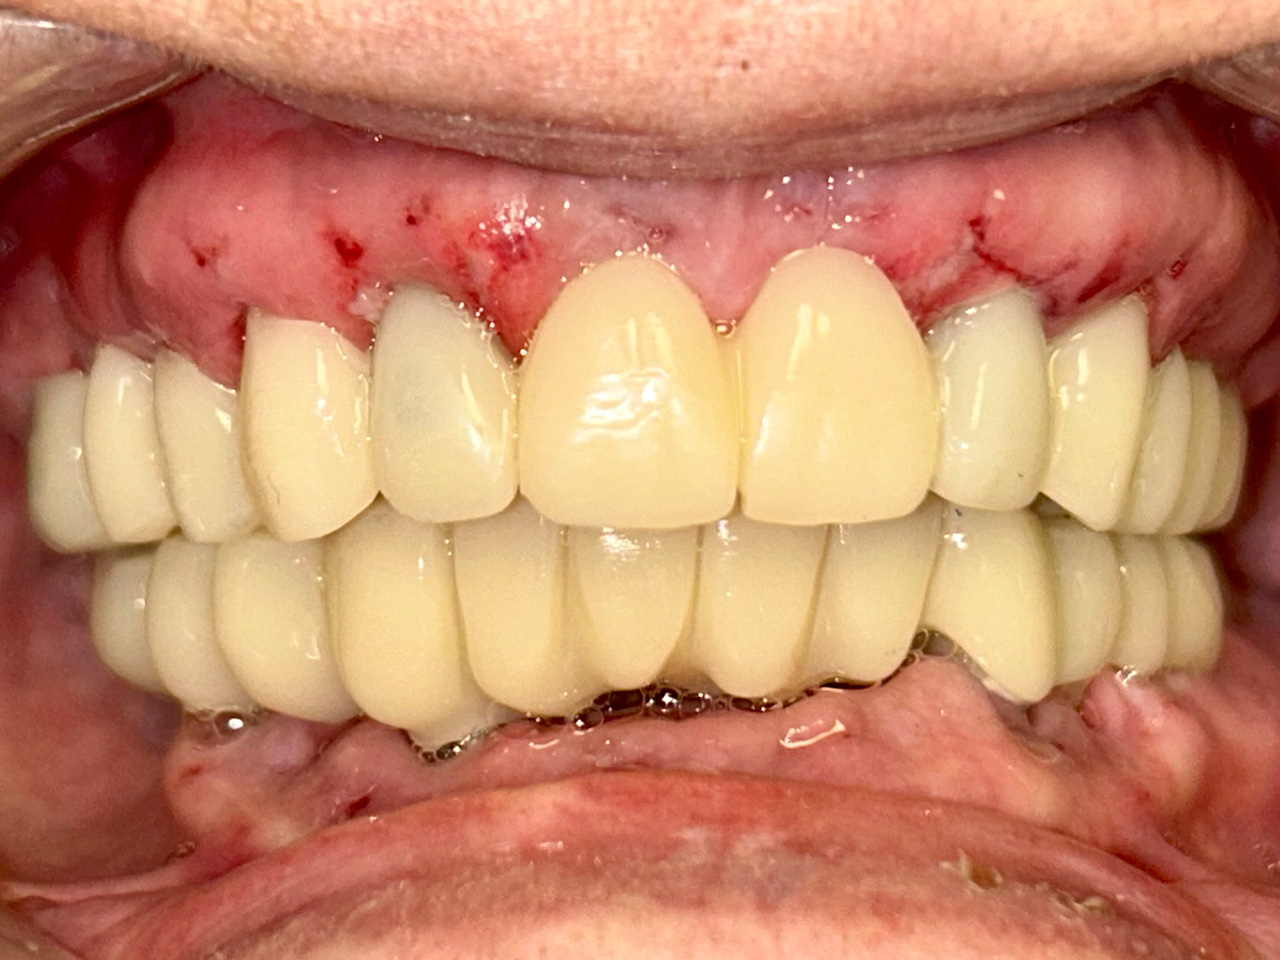

Elhanyagolt fogsor cseréje 2 nap alatt

2 nap alatt varázsoltuk ezt a szép esztétikus alsó, felső körhídat implantátumokkal megtámasztva a korábban elhanyagolt szájba. Az 1. nap 26 fogat távolítottunk el, mert annyira rossz állapotban voltak, és rögtön azonnal terhelhető IHDE svájci implantátumokat raktunk be, fentre 8, lentre 6 darabot. A sebeket összevarrtuk és intraorális szkennerrel digitális lenyomatot vettünk. 2 nap múlva pedig beragasztottuk a kész PMMA műanyag körhidakat. Dr. Kelemen Péter és a Symbion Fogtechnika munkája.